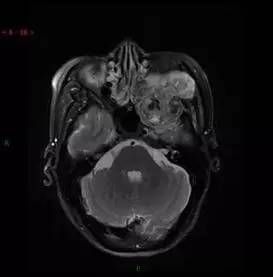

MRI增强轴位

解析:本病例为中颅窝至颞下窝沟通性病变,对周围骨质主要呈膨胀压迫性改变,伴囊变、出血。

病理:(中颅底内外沟通肿瘤) 神经鞘瘤,伴出血,局灶细胞较丰富。免疫组化结果显示:EMA(-), P53(-), S100(3 ), NF(-), PR(-), desmin(-), Ki-67( ,5-10%)

神经鞘瘤

总之,颞下窝原发肿瘤病种丰富,良性肿物多边界清晰,周围骨质多为压迫性骨质吸收变形。恶性肿瘤边缘模糊,内可见坏死,邻近骨质破坏。在临床工作中,如见肿瘤呈颅内外沟通生长的哑铃型,一般首先考虑神经源性肿瘤。有时脑膜瘤也会出现颅内外沟通生长的表现。肿瘤边界清楚,肿瘤T2WI以低信号为主,则考虑纤维来源的肿瘤如孤立性纤维性肿瘤可能。如肿瘤有很强的侵袭性,并沿神经生长,密度较低,见缝就钻,应考虑腺样囊性癌可能。如肿瘤边界清楚,轻度强化,内可见血管穿行,应考虑淋巴瘤的可能。颞下窝肿瘤的表现多样,具体问题具体分析,但抓住病变的重要特征为基点进行思考,是肿瘤诊断和鉴别诊断的有效方式之一。